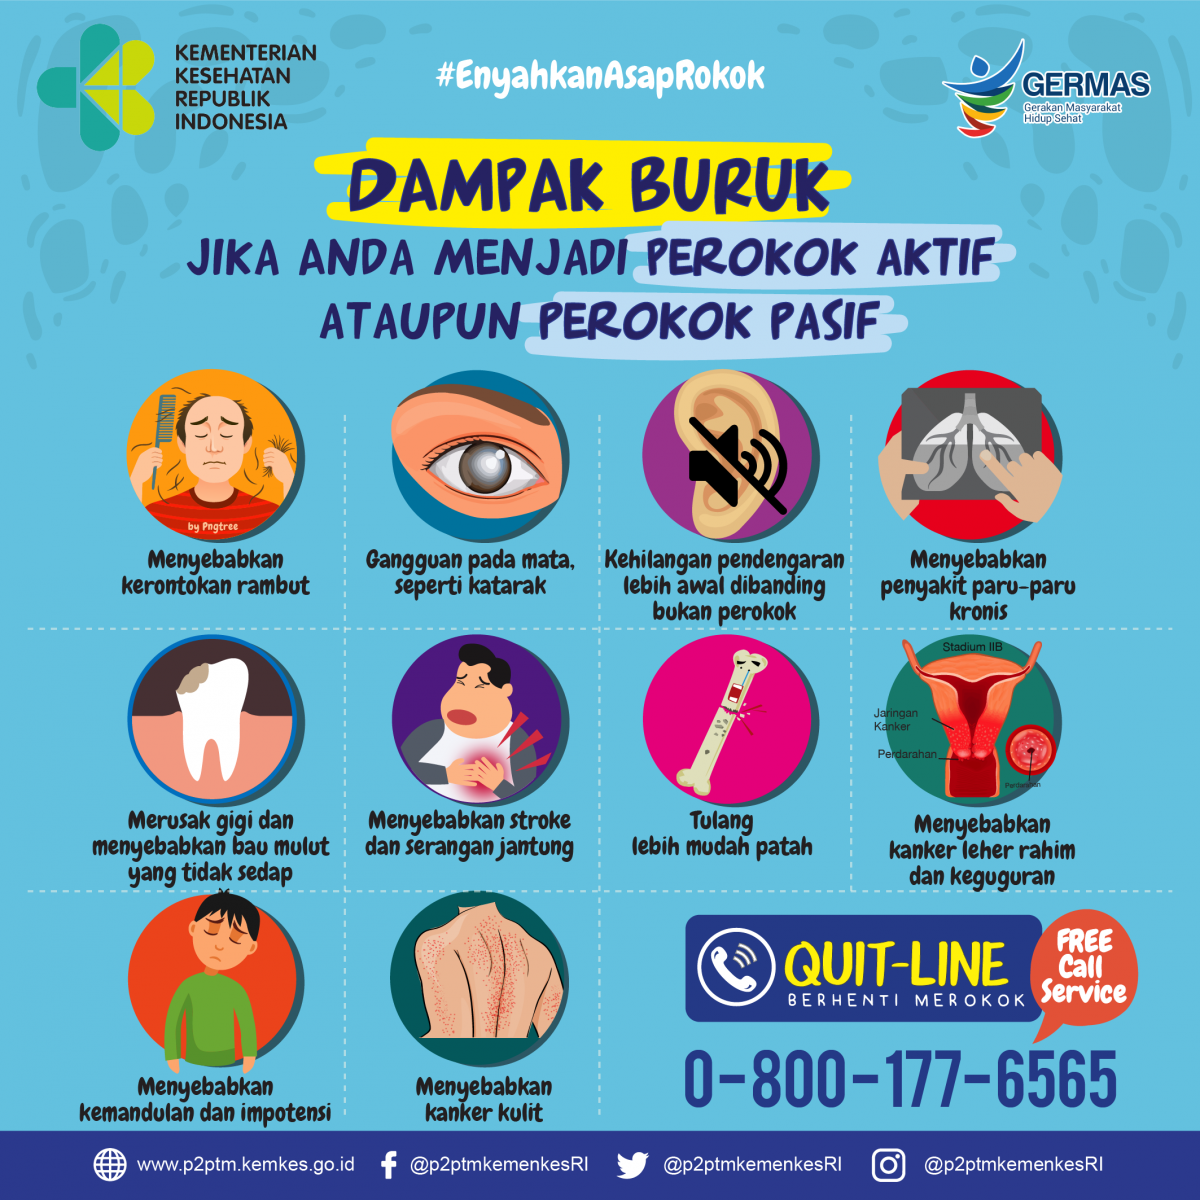

Dampak Buruk Jika Anda Menjadi Perokok Aktif Maupun Perokok Pasif Direktorat P2ptm

Dampak Buruk Jika Anda Menjadi Perokok Aktif Maupun Perokok Pasif Direktorat P2ptm